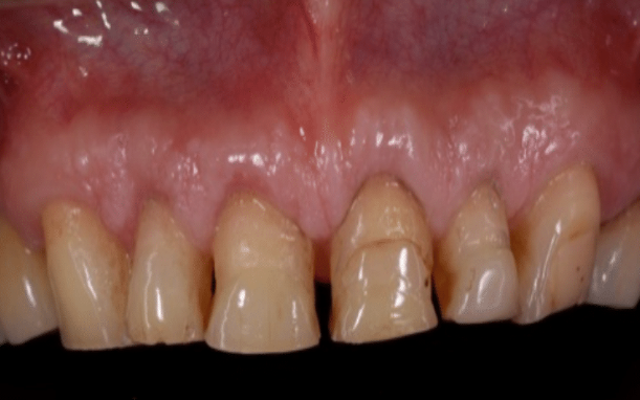

Following crown lengthening, the gum has been repositioned to expose enough tooth structure for restoration with crowns.

The teeth have now been restored with long lasting crowns.